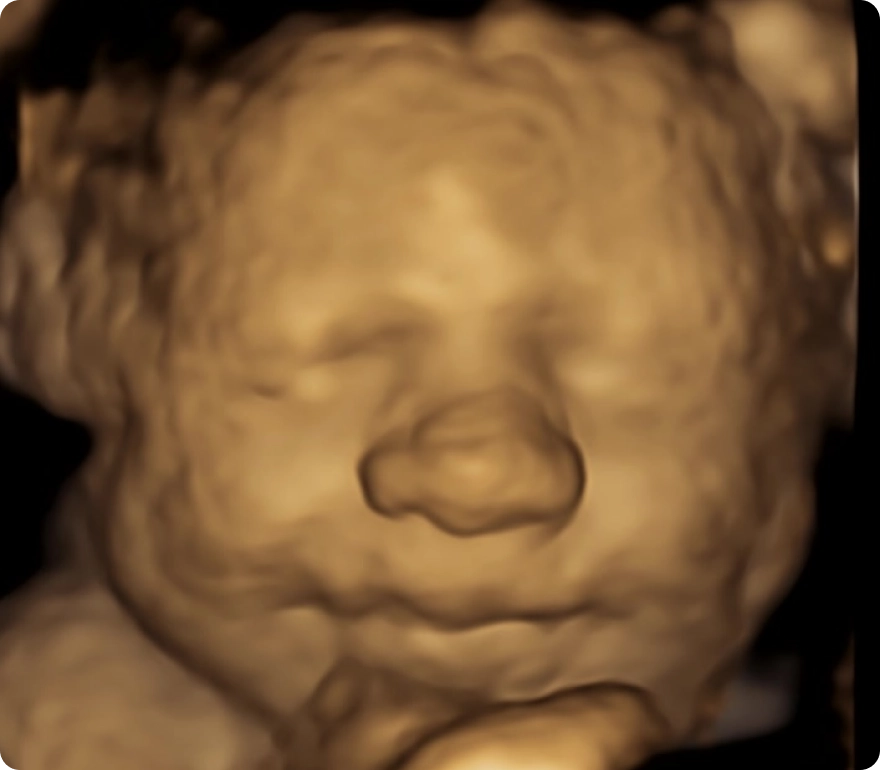

Our advanced HD ultrasounds offer breathtaking clarity and detail, allowing you to see your baby like never before. Every image and movement becomes a memory—one you can share and treasure for a lifetime.

Our state-of-the-art ultrasound technology gives you a front-row seat to your baby’s world. From tiny yawns and gentle stretches to blinking, swallowing, and little finger wiggles, our 3D, 4D, and HD ultrasounds capture these once-in-a-lifetime moments with stunning clarity and detail.

Advanced technology with stunning clarity, color, and detail—offering the most realistic, lifelike view of your baby before birth.